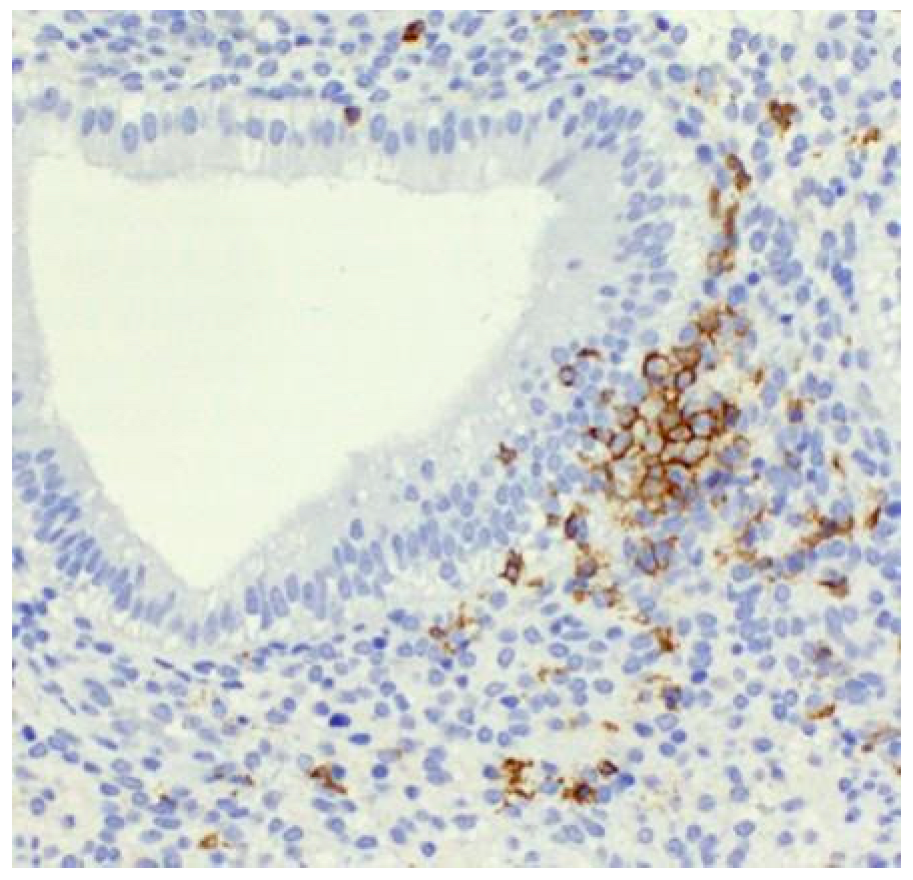

Clustering of Uterine Natural Killer Cells Around Uterine Glands in Women with Recurrent Implantation Failure and Recurrent Pregnancy Loss: An Immunohistochemical Study

- Lapides, L.; Varga, I.; Klein, M.; Rybánska, L.; Belušáková, V.; Babál, P. When Less Is More—Pipelle Endometrial Sampling for Quantification of Uterine Natural Killer Cells in Patients with Recurrent Implantation Failure or Habitual Abortion. Physiol. Res. 2022, 71, S65–S73. [Google Scholar] [CrossRef]

- Lapides, L.; Klein, M.; Belušáková, V.; Csöbönyeiová, M.; Varga, I.; Babál, P. Uterine Natural Killer Cells in the Context of Implantation: Immunohistochemical Analysis of Endometrial Samples from Women with Habitual Abortion and Recurrent Implantation Failure. Physiol. Res. 2022, 71, S99–S105. [Google Scholar] [CrossRef]